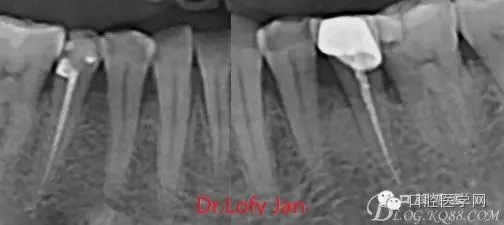

前言:自己做的一些曲面斷層片在未試尖根管治療中的病例整理,發(fā)現(xiàn)問題很多包括自身的,技術(shù)的,還有設(shè)備的問題,予以總結(jié)整理并期待進(jìn)一步提高。

根管治療術(shù)是牙體牙髓疾病治療中最復(fù)雜和最關(guān)鍵的治療項(xiàng)目。根管充填材料抵達(dá)根尖、并能嚴(yán)密堵塞根尖孔,是確保根管治療效果的關(guān)鍵指標(biāo)。為了保證根管充填到位,醫(yī)生需要在術(shù)前照牙片以了解牙根根管的數(shù)量、彎曲程度和長度,在術(shù)中有時(shí)需要插針照牙片來精確測量根管長度,術(shù)后必須照牙片以確定是否根管充填到位,如果欠填或超填,就需要重新充填、重新照牙片確認(rèn),直到根管充填到位。所以,在患者接受根管治療時(shí)有時(shí)會反復(fù)照牙片。

病例分析:曲面斷層片在x線輔助診斷與檢查中目前大多數(shù)文獻(xiàn)和著作都建議只能作為初診拍片檢查手段,不能作為終末疾病的確診與手術(shù)療效的評價(jià)指標(biāo),臨床大部分中小型門診都因?yàn)樵O(shè)備不齊全導(dǎo)致信息偏差很大。